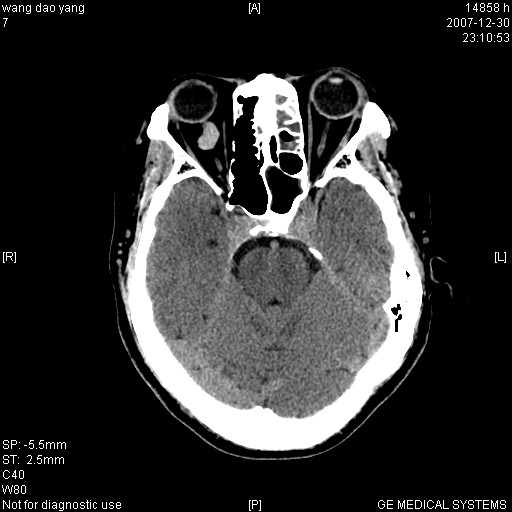

因外伤做ct

1。左侧筛窦蝶窦少量积液,2。右眼眶视神经鞘瘤可能性大,建议增强一下

肌圆锥内占位性病变,血管瘤可能性大。

1 病灶位于肌圆锥内,从第一帧看,和视神经关系不紧密。

2 病灶边界光整,形态欠规则。

3 病灶密度明显高于同层面的正常软组织。

外伤的话首先考虑球后血肿!!

病灶形态不规则,临床有外伤史,支持考虑:球后血肿!!!

考虑右侧视神经脑膜瘤或血管瘤,建议增强进一步检查。

考虑右侧视神经脑膜瘤或视神经胶质瘤,建议增强进一步检查鉴别。

考虑右侧视神经鞘瘤,脑膜瘤或纤维瘤。

球后肌锥内小团块状软组织密度影(性质待定);建议:行ct增强扫描或mri检查。